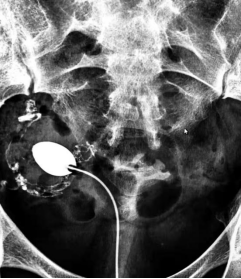

什么是子宫输卵管造影?

子宫输卵管造影(HSG)是指将造影注入子宫腔内,通过X-线观察记录造影剂的流动的过程,显示子宫、输卵管内腔的形态,以及造影剂流入腹腔后的弥散情况,从而对子宫输卵管形态功能做出诊断的不孕症检查措施。HSG是女性不孕症的初始检查之一,具有不可或缺的诊断价值。